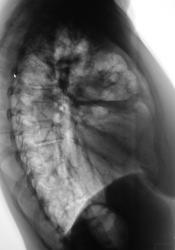

Но смутила конфигурация сердечной тени. Глянул в "сиаре" архив. 6 месяцев тому производили пациентке снимки - "состоит на учете" у кардиолога по поводу открытого боталлова протока и дефекта межпредсердной перегородки.

Ниже представлены фрагменты рентгенограмм с увеличением и томограммы, произведенные в прямой проекции.

Ниже представлены томограммы правого лёгкого в боковой проекции.

Создаёться впечатление, о пневмонии в S4 справа;дефигурация сердца.

Огромная полость в передних отделах верхней доли правого легкого с тонкими стенками и мениском жидкости, хорошо дренированная - возможно ВСЁ  :)

Все равно сомнения: рак с распадом?, твс каверна с аспергилломой?, абсцесс с секвестром? Тут кавалерийским наскоком боюсь у нас  не получится. Дальше по кругу, вернее - "Бермудский треугольник" онко пульмо и твс диспансеры... Есть огромный риск легочного кровотечения - гипертензия в малом круге, необходимо предупредить лечащего врача...

Уже вызвали консультантов из области. Сами с учетом предыдущих рентгенограмм, кстати, были и томограммы, предположили, что имеется абсцедирование, возможно несколько полостей, которые слились между собой. "Запашок" помог в проведении "предварительной" дифференциальной диагности. "Запашок", как при "хорошем" абсцессе или гангрене лёгкого. Конечно, больная затяжелела, наслоилось все "друг на друга" и сердечная симптоматика (пороки) и сосудистая, ну и легочная.

А раз клиника гангрены - это наверное позволяет уменьшить вероятность твс, но рак дренирующего бронха не исключаем... Прогноз в любом случае печален... :(

Картина (полость с экссудативным компонентом) характерна для пневмонии, вероятно стафилококковой природы.